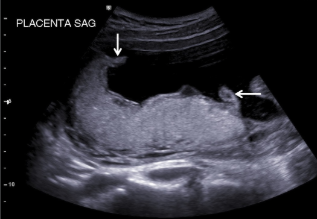

What are the arrows pointing to?

circumvallate/circummarginate placenta